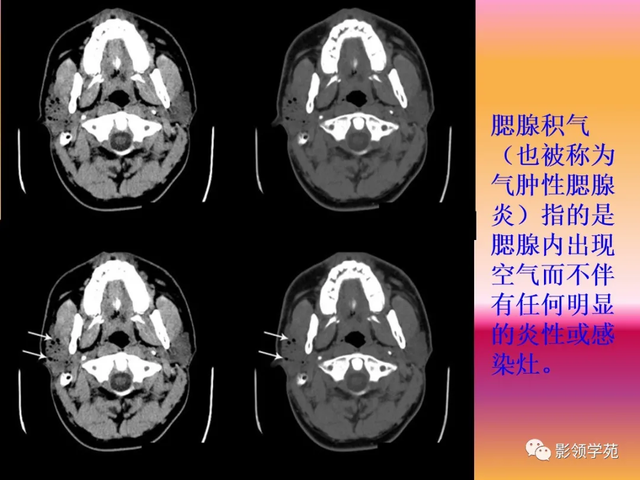

当腮腺炎症合并蜂窝织炎时,体现为腮腺弥漫性肿大并普遍 气体影;